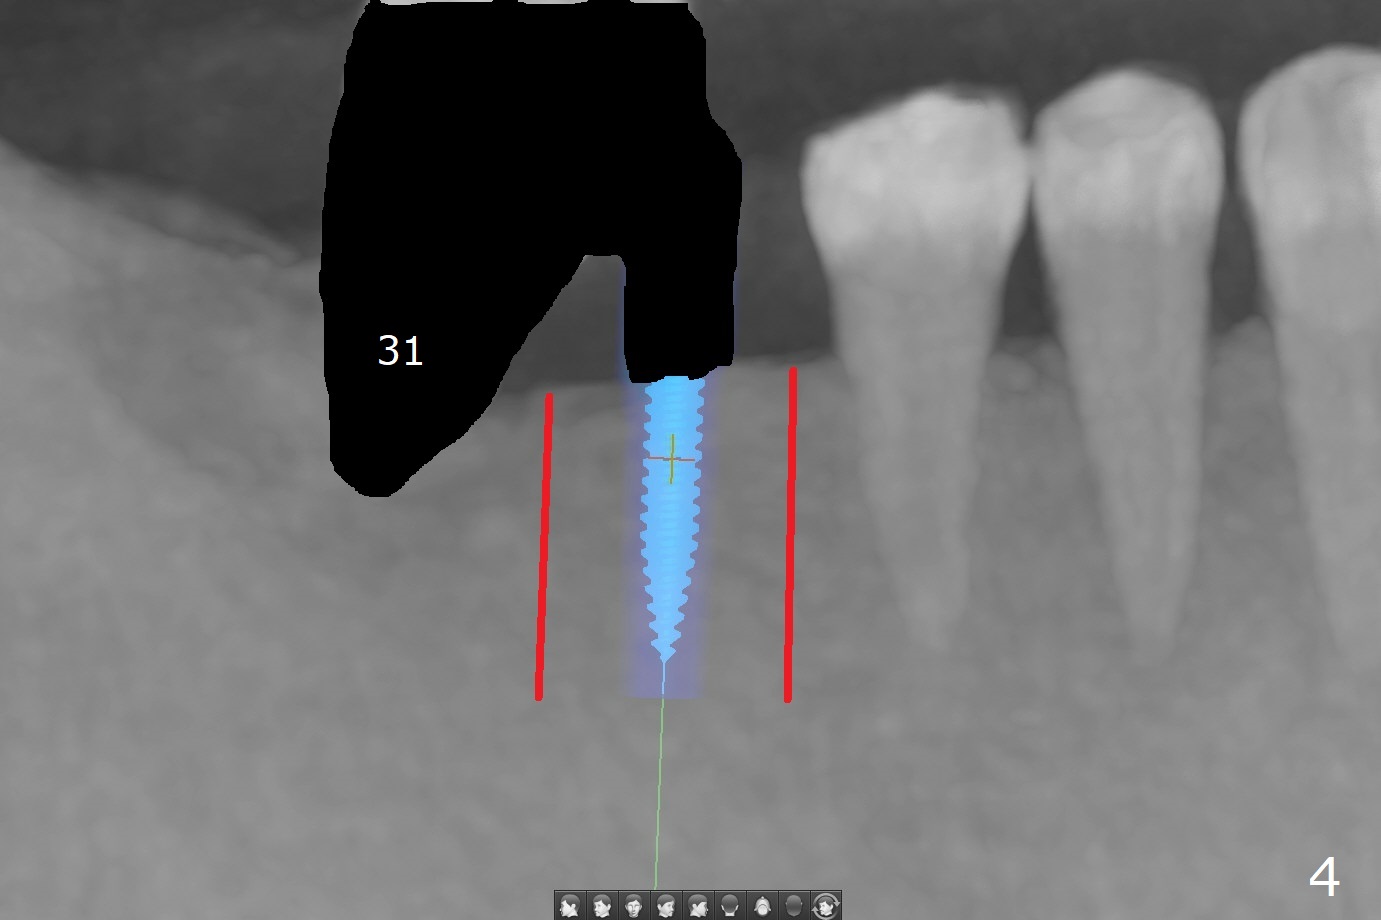

Several months post #31 socket preservation, the narrow ridge of #30 (Fig.1 (CT 3-D occlusal view), 6 (coronal section)) will be exposed with a crestal and 2 oblique incisions, followed by osteotomy with a 2 (2.2) mm drill (green) and a surgical guide. A crestal transverse cut will be conducted using a surgical fissure bur (Fig.2 red), followed by 2 vertical cuts (Fig.3,4 (3-D X-ray mode, buccal view) and an apical transverse one (Fig.5,6). The incision will be closed. Three weeks later, a crestal incision will be made. The buccal plate will be fractured and pushed buccal (Fig.7,8 arrow) using chisel (yellow). The guide will be reseated for osteotomy, implant placement (Fig.9 green) and bone graft. In fact there is not much problem when the osteotomy moves lingual.